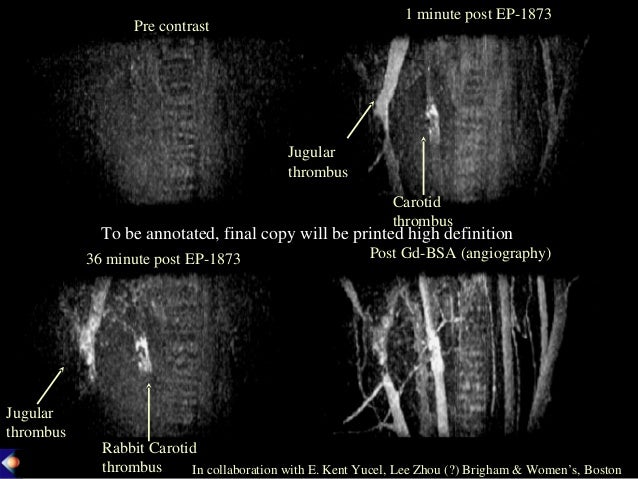

Magnetic Resonance Imaging (MRI) is a medical imaging procedure for making images of the internal structures of the body. Gadolinium-Based Contrast Agents (GBCA) are intravenous drugs used in diagnostic imaging procedures to enhance the quality of magnetic resonance imaging (MRI) or magnetic resonance angiography (MRA).

To report any unexpected adverse or serious events associated with the use of this drug, please contact the FDA MedWatch program listed below.Radiographic contrast has been used for over a century to enhance the contrast of radiographic images. Gadolinium-based contrast agents are rare earth metals that are usually given through an IV in the arm.įor more information about MRI and their safety and risks, please see the Center for Radiological Health’s consumer information page. A typical MRI scan last from 20 - 90 minutes, depending on the part of the body being imaged.įor some MRI exams, intravenous (IV) drugs, such as gadolinium-based contrast agents (GBCAs) are used to change the contrast of the MR image. Radio waves are sent from and received by a transmitter/receiver in the machine, and these signals are used to make digital images of the scanned area of the body. The signal in an MR image comes mainly from the protons in fat and water molecules in the body.ĭuring an MRI exam, an electric current is passed through coiled wires to create a temporary magnetic field in a patient’s body. MRI scanners use strong magnetic fields and radio waves (radiofrequency energy) to make images.